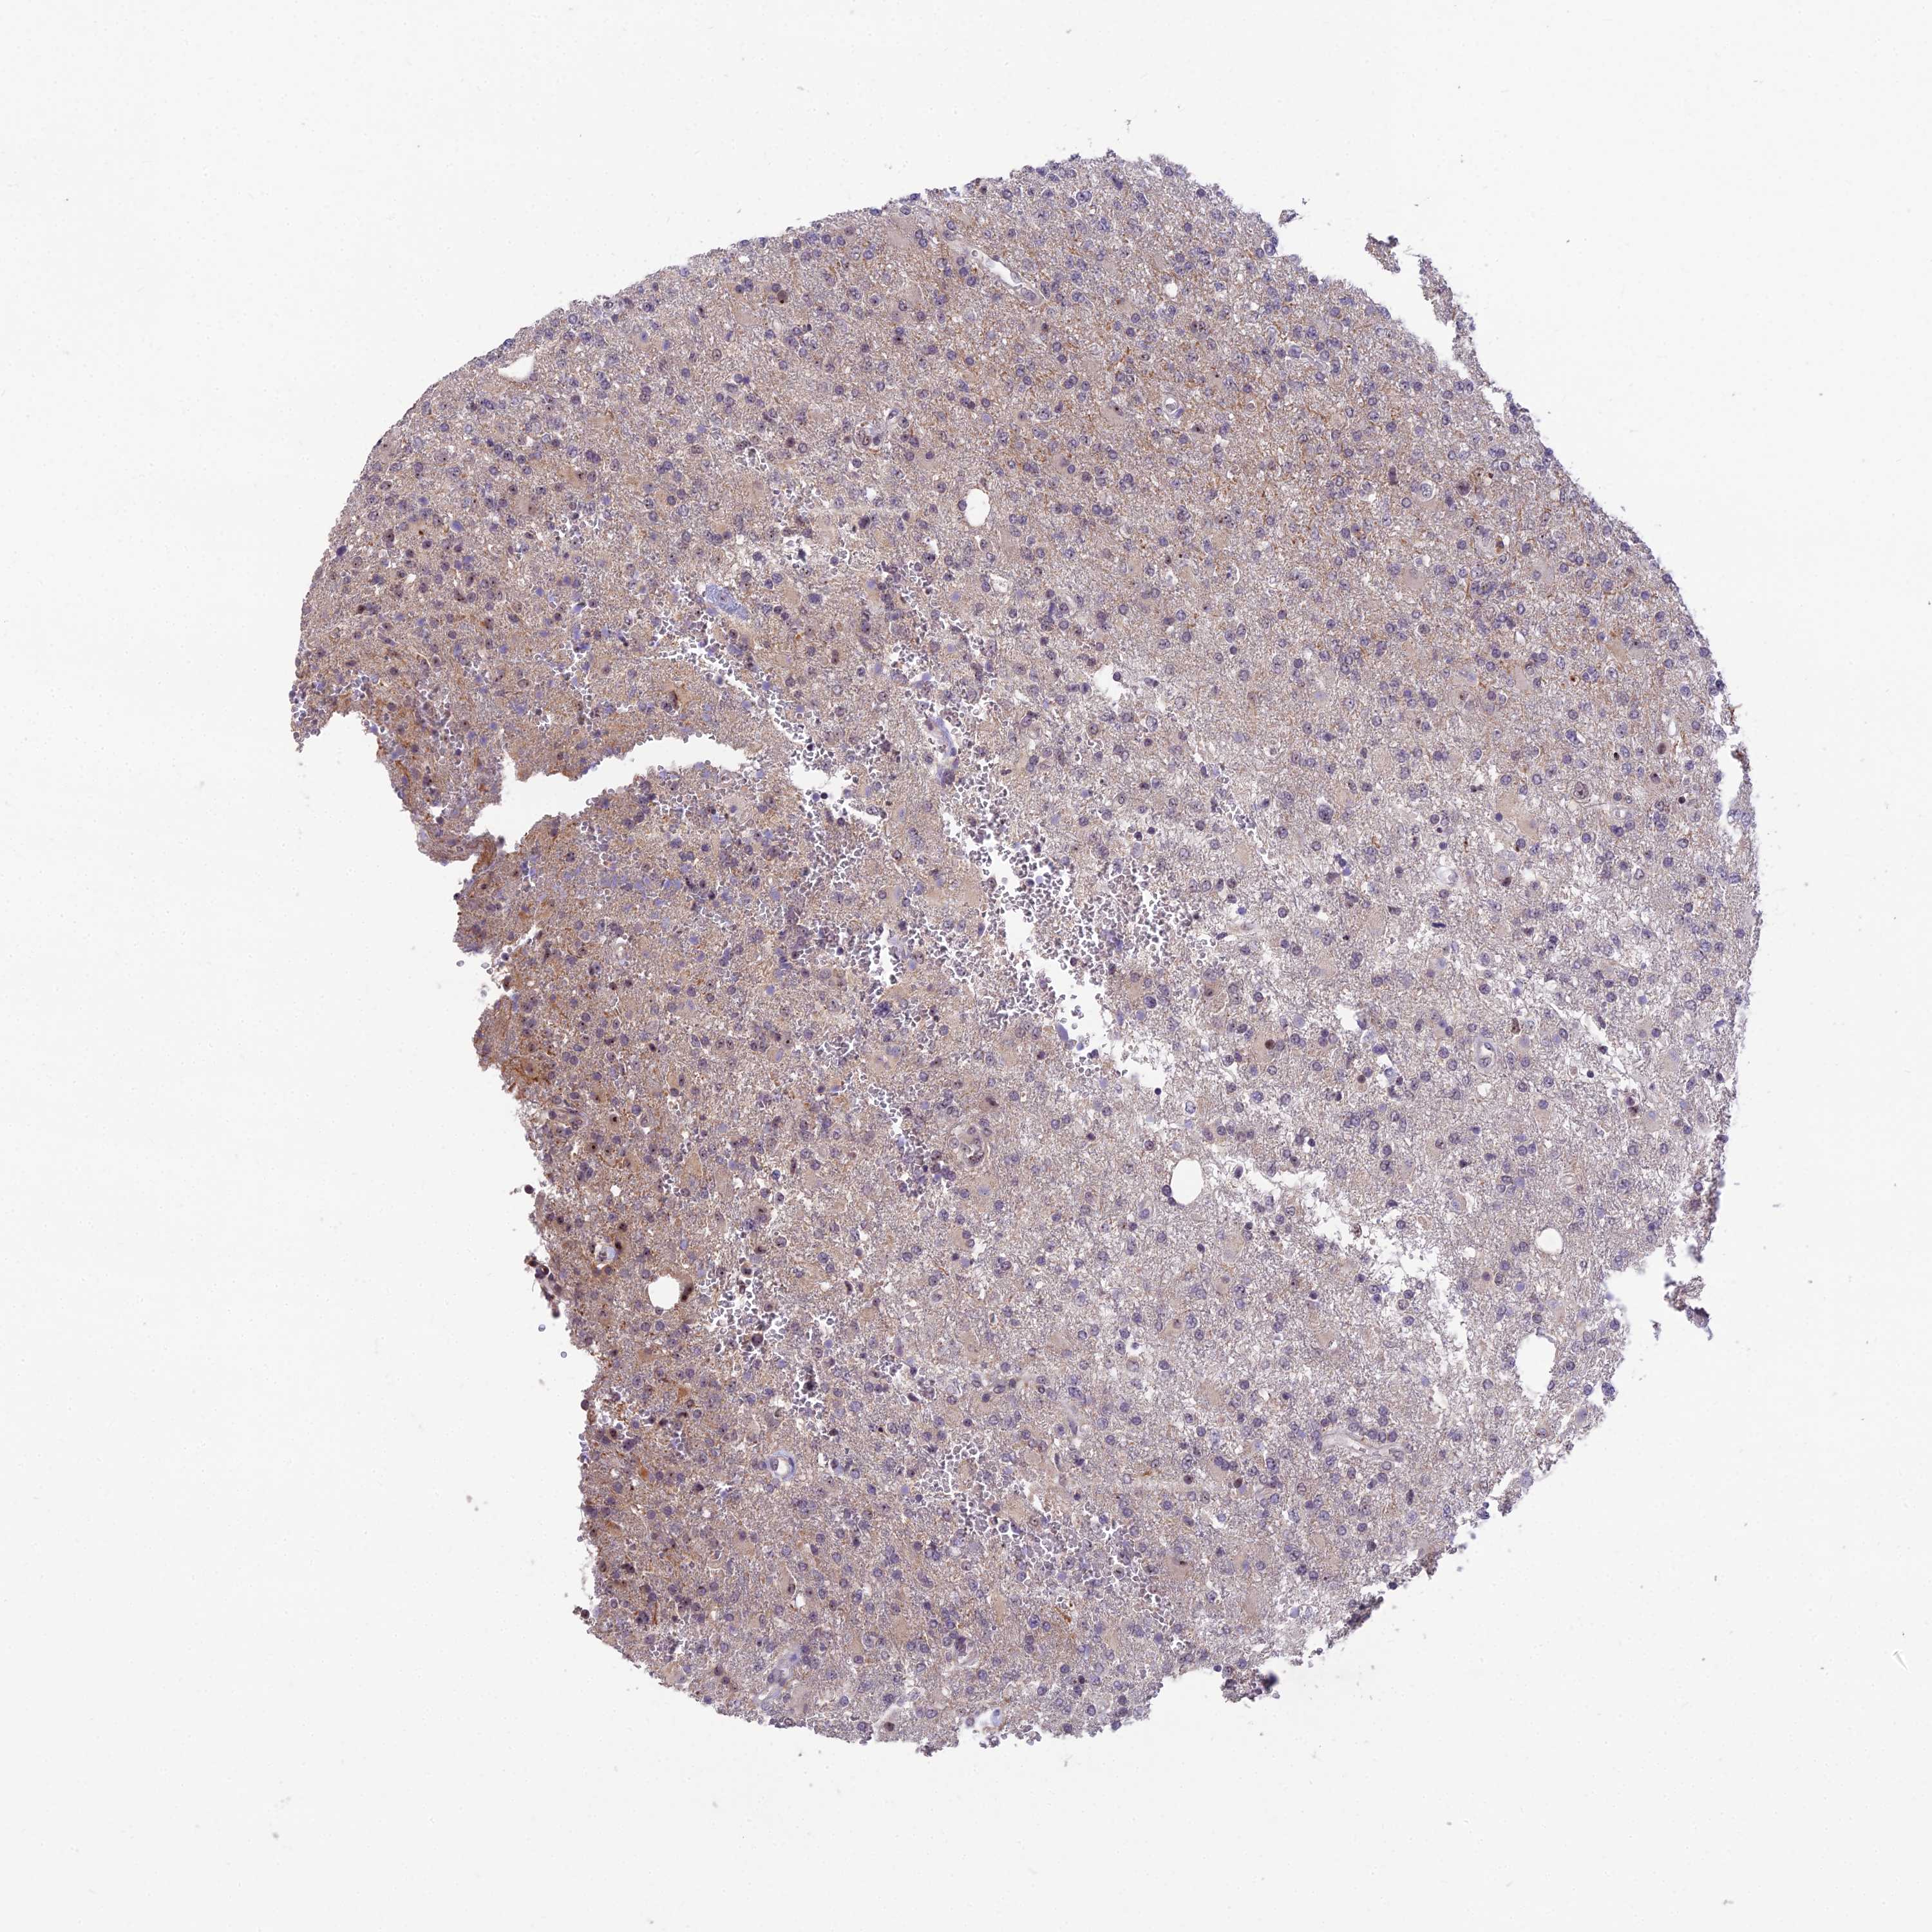

GLIOMA - Protein expressioni

A mouse-over function shows sample information and annotation data. Click on an image to view it in a full screen mode. Samples can be filtered based on level of antibody staining by selecting one or several of the following categories: high, medium, low and not detected. The assay and annotation is described here.

Note that samples used for immunohistochemistry by the Human Protein Atlas do not correspond to samples in the TCGA dataset.

Antibody stainingi

Antibody staining in the annotated cell types in the current human tissue is reported as not detected, low, medium, or high, based on conventional immunohistochemistry profiling in selected tissues. This score is based on the combination of the staining intensity and fraction of stained cells.

Each image is clickable and will lead to virtual microscopy that enables deeper exploration of all samples and also displays staining intensity scores, fraction scores and subcellular localization as well as patient and tissue information for each sample.

Antibody HPA043973

Staining

High

Medium

Low

Not detected

Intensity

Strong

Moderate

Weak

Negative

Quantity

>75%

75%-25%

<25%

None

Location

Nuclear

Cytoplasmic/membranous

Cytoplasmic/membranous,nuclear

Glioma, malignant, High grade

Glioma, malignant, Low grade